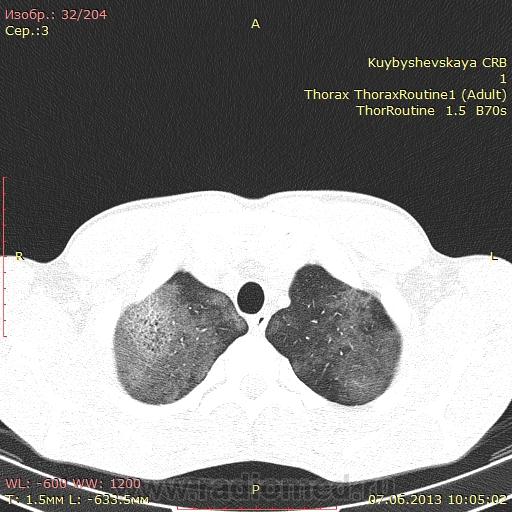

здравствуйте. помогите пожалйста с диагнозом. пациент 1983 года рождения. поступил 27.05. температура до 38, одышка. по рентгенограммам правостороняя верхне среднедолевая пневмония, очаговые тени слева. консультирован фтизиатром.данных за Tbc нет.

Чего же только правостороння - двусторонняя полисегментарная, больше справа, преимущественно верхнедолевая пневмония, насколько понимаю.

Не мудрено, что ////консультирован фтизиатром.данных за Tbc нет.////. КТ-данных заТВС тоже нет. Уплотнение по типу "матового стекла", преимущественно в верхних долях и центральных отделах. Острая двусторонняя интерстициальная пневмония, как вариант, цитомегаловирусная, а может и пневмоцистная (если имеется ВИЧ/СПИД)

Картина интресная- абсолютно интактен плащевидный слой лёгкого, изменения в ядероном слое верхнего и среднего лёгочных полей. Если имеет место интерстициальная пневмония, тогда почему не видим рисунок (паттерн ) поражения интерстиция-сетчатый рисунок интерстициального каркаса лёгкого?

На первое место все-таки нужно ставить интерстициальную пневмонию специфического происхождения (пневмоциста, микоплазма, т.п.), хотя у меня, если честно, душа к этому диагнозу не лежит. Какая-то слишком четкая граница между пораженными и непораженным участками... И почему-то периферческие отделы почти не поражены. Может оказаться на самом деле альвеолярный протеиноз: http://radiopaedia.org/articles/pulmonary-alveolar-proteinosis

Для альвеолярного протеиноза, на сколько я знаю характерна картина "crazy paving" (она же булыжная мостовая, сумасшедшее мощение, сумасшедшая исчерченность(по Юдину)). это когда много участков матового стекла а на фоне их ретикулярная исчерченность - усиления меджолькового и центрального интерстиция, в данном случае мы имеем меж-/внутридольковый интерстиций в верхней доле справа только. хотя вполне возможно что поймали протеиноз в начале...) но я больше склоняюсь к 2 вариантам: ОсИП (Хаммена-Рича), в данном случае как неспецифическое проявление ОРДС(енобходимо выяснить какой агент вызвал), либо же это ДИП (может больной курит много и т.п.), или жу у пациента иммунодиффицит, что точно показали бы анализы, которые наверняка не раз сделали. Необходимо детально опросить пациента, чтоб проверить первые 2 варианта и провести микроскопию бронхо-альвеолярного лаважа (при правильном проведении найдутся или протеины, или макрофаги, или лейкоциты)

пациент сдал кровь на ВИЧ. результат положительный. так что скорее пневмоцистная пневмония